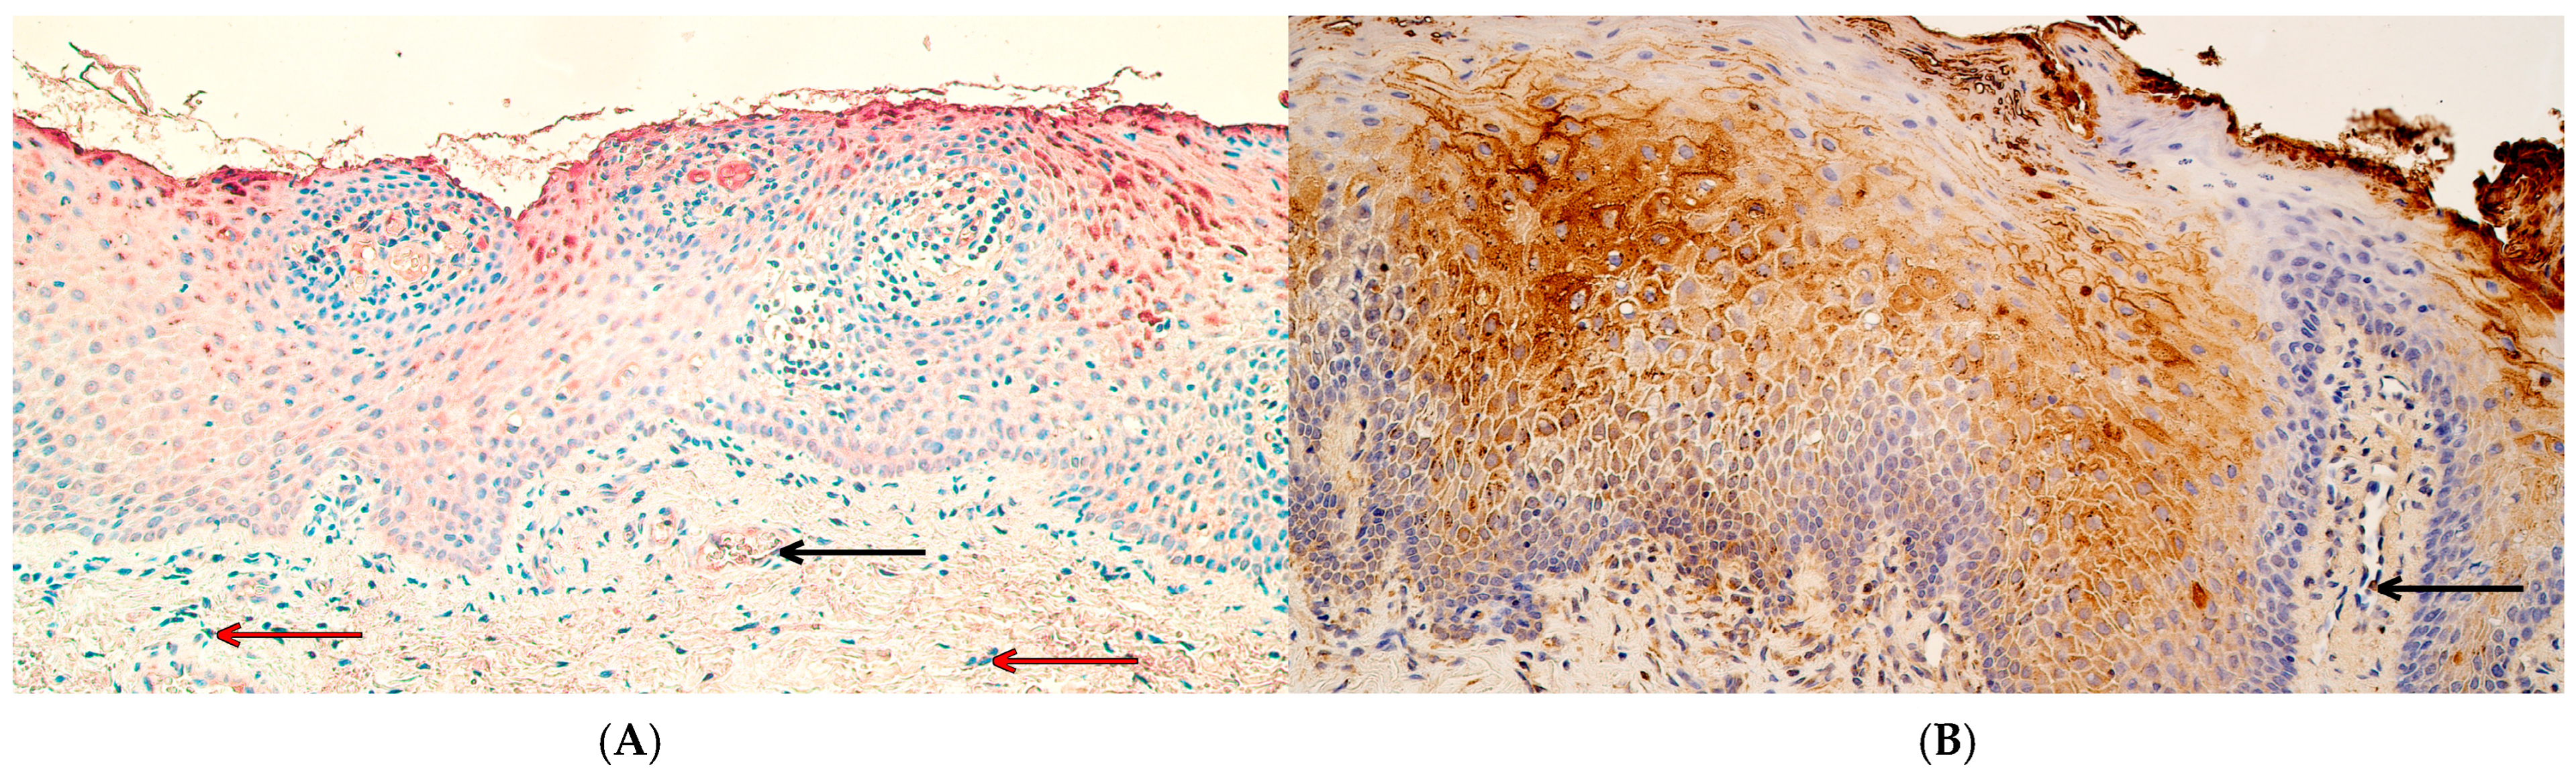

2.2. Chromogenic In Situ Hybridization

3.3. The Number of MSX2 and RYK Gene-Signal-Containing Cells Was Significantly Increased in Cleft Lip Tissue While the Number PTX3 Gene-Signal-Containing Cells Did Not Differ from Controls